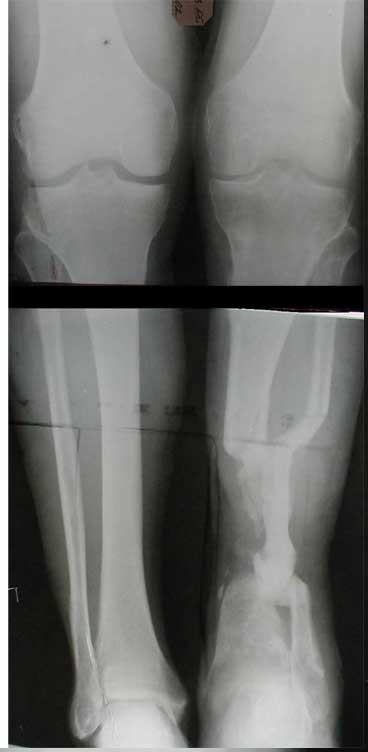

1. Chto kasaetsa snimkov bolnogo to oni budut segodnjia v horoshim digital forme,

2. segodnjia ja pereviazival bolnogo pod GA, stopa zivaja, teplaja, hot' i otekaet sylno iz za "vidimo" narushenjia venoznongo atoka,

3. Chto menjia smushet: kak ja smogu sdelat' "bone trasport" v budeshim, esli znat', chto anatomia ochen' sylno izminilas', i kazitsa, chto a. tibialis anterior, prosto nahoditsa v prostranstve mezhdu otlomkami tibia, VOPROS: Sleduet li sdealat' reviziyu ee na dalnishih pereviazkah, chto bi transpozirovat' ee? Ili ne nuzhno ito sdelat'? Budet li promezutochny fragment otodvigat' ee peremishes' vniz ILI ona zashemitsa mezdu otlomkami?

4. Aktivnih dvizhenjia v golenostopnom sustave NET! no poka rano ob itom sudit' okonchatrelno.

5. Ne tolko zadnjia poverhnost' otkritajia, est' chast' kosty na protezenjii okolo 4-h cm. obnazena po peredne-vnutrennoi poverhnoste Prox. kones tibia".